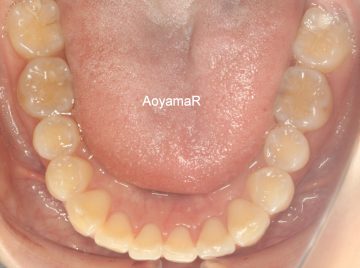

治療後